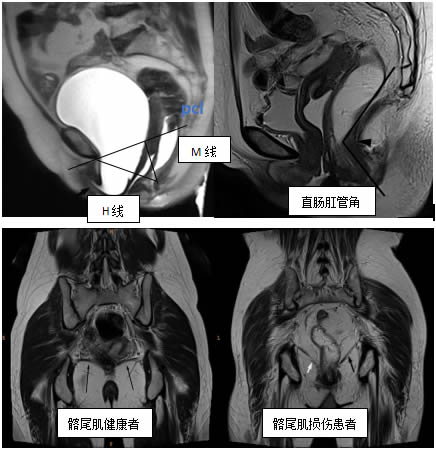

精準評估

評估靜息態及動態時的直腸肛管角、H線、M線等,雙側髂骨尾骨肌、恥骨尾骨肌(jī)、恥骨直腸肌(jī)、提肌平麵等盆底(dǐ)支持(chí)結構,借助PCL輔助線(xiàn)診斷盆底器官的脫垂等情況。